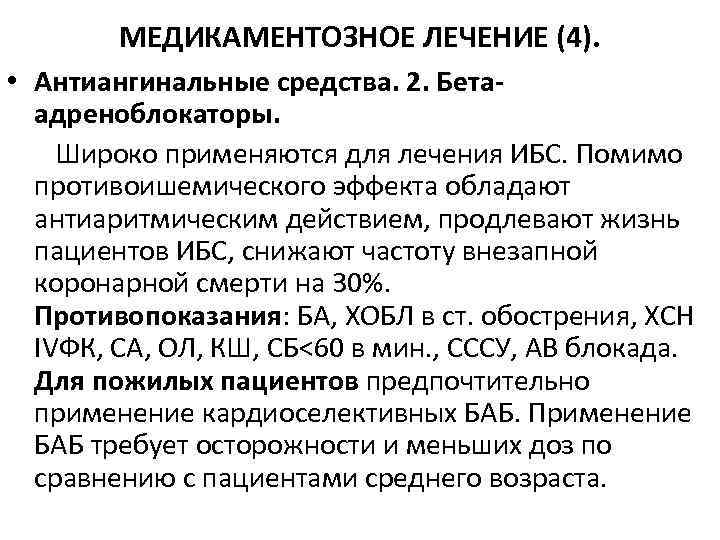

МЕДИКАМЕНТОЗНОЕ ЛЕЧЕНИЕ (4). • Антиангинальные средства. 2. Бетаадреноблокаторы. Широко применяются для лечения ИБС. Помимо противоишемического эффекта обладают антиаритмическим действием, продлевают жизнь пациентов ИБС, снижают частоту внезапной коронарной смерти на 30%. Противопоказания: БА, ХОБЛ в ст. обострения, ХСН IVФК, СА, ОЛ, КШ, СБ<60 в мин. , СССУ, АВ блокада. Для пожилых пациентов предпочтительно применение кардиоселективных БАБ. Применение БАБ требует осторожности и меньших доз по сравнению с пациентами среднего возраста.